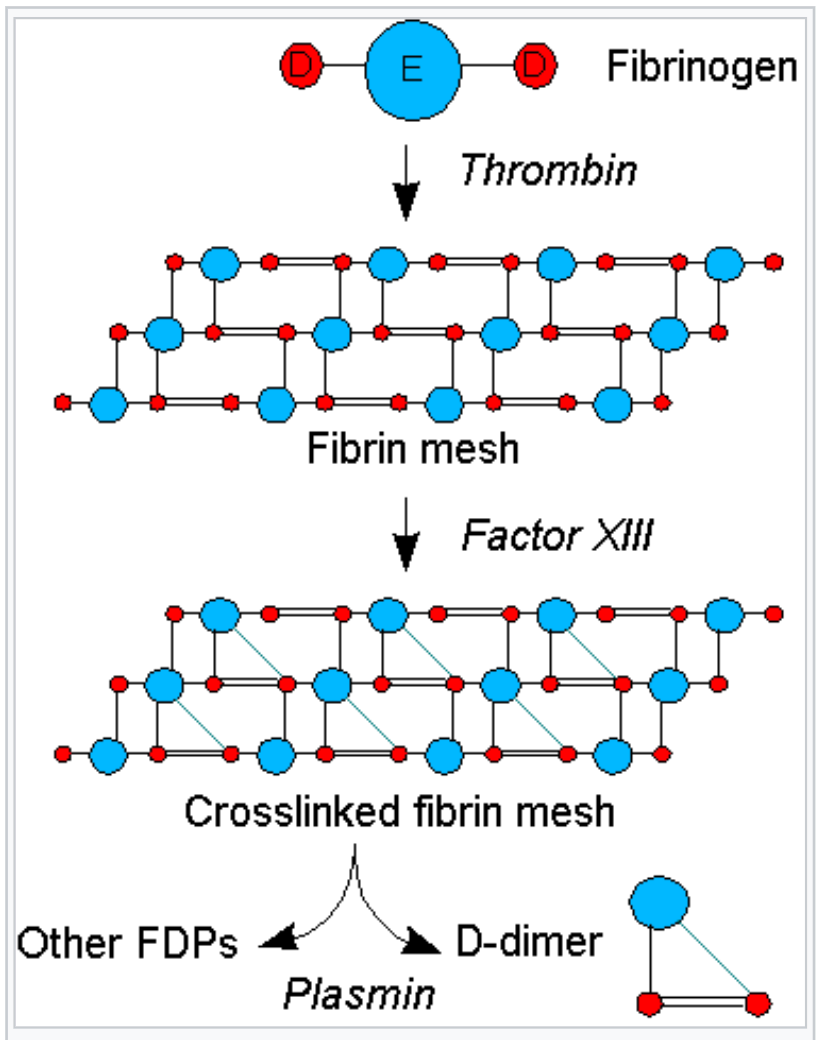

In this podcast, we talk with Dr. Robert Young who explains the significance of the D-dimer blood test as it relates to Covid-19 disease, pathological coagulation and blood clots leading to hypoxia and death. Click on the link below or any of the diagrams to listen and learn more about the D-dimer blood test and pathological blood clotting.

Understand Why Blood Clots Form Inside the Blood Vessels!

Read Dr. Robert O. Young’s Peered Review Scientific Research Article Published in the International Journal of Vaccines and Vaccination on Pathological Blood Coagulation! (2016)

Pathological Blood Coagulation and the Mycotoxic Oxidative Stress Testing, Young RO (2016) Pathological Blood Coagulation and the Mycotoxic Oxidative Stress Test (MOST). Int J Vaccines Vaccin 2(6): 00048. DOI: 10.15406/ijvv.2016.02.00048